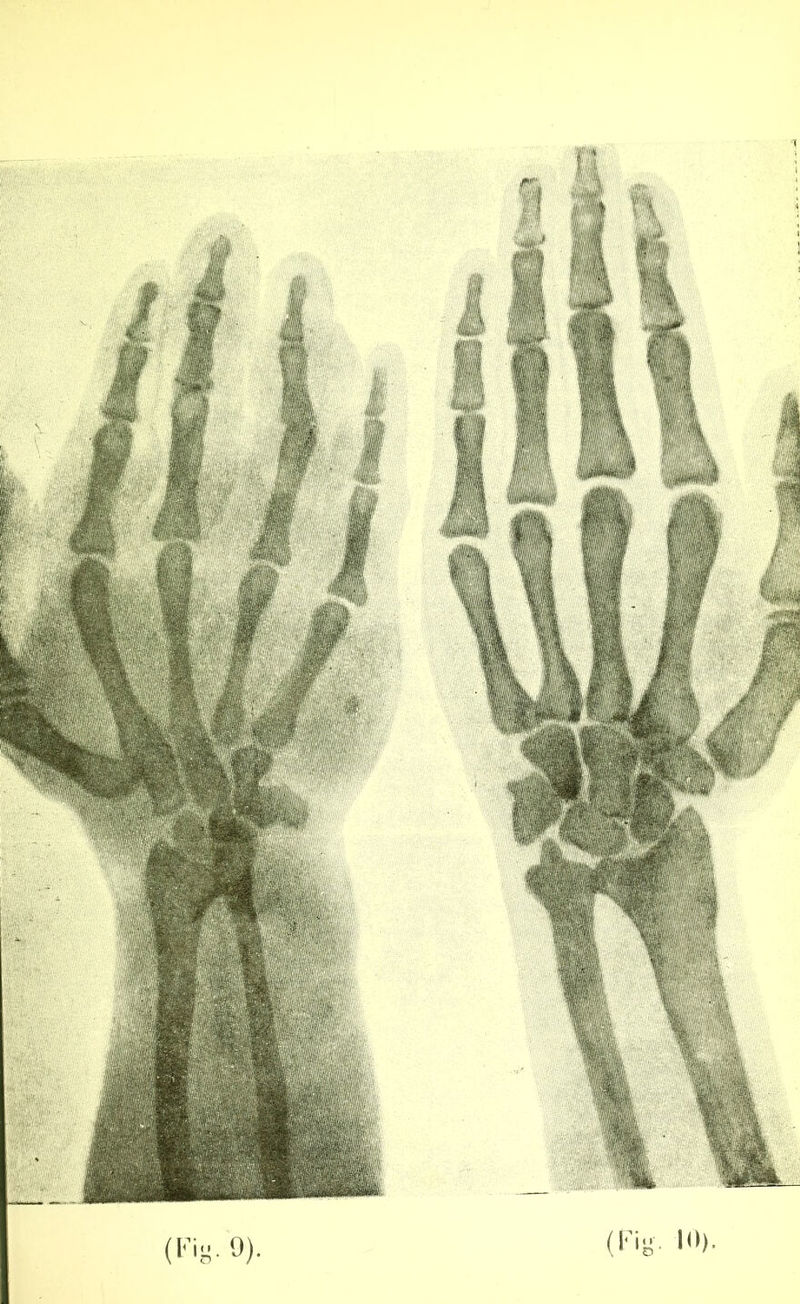

Trois cas de phlébectasie congénitale de l'extrémité supérieure / par Alexandre Pacha Kambouroglou.

Credit: Trois cas de phlébectasie congénitale de l'extrémité supérieure / par Alexandre Pacha Kambouroglou. Source: Wellcome Collection.